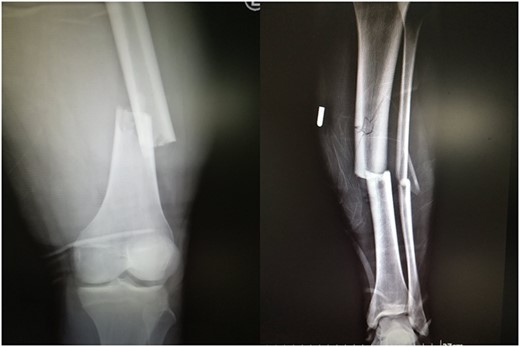

A 19-year-old male patient was admitted to the orthopedic department of our institution after a motorbike accident. The patient sustained a diaphyseal fracture of the left femur and ipsilateral tibia (floating knee) (Fig. 1), along with a right acromioclavicular joint type II injury and a right minimally displaced distal radius fracture. The patient was scheduled for emergent surgery. He underwent a retrograde intramedullary nailing of the left femur and an antegrade intramedullary nailing of the left tibia, under general anesthesia (Fig. 2). The operation was performed with the patient in the lithotomy position. The right intact leg was applied in 1000 of the hip flexion and 900 of the knee flexion. The duration of the surgery was 4 h and 20 min.

Post-operative view of the left femur and tibia. Concomitant retrograde IM nailing and antegrade IM nailing were performed.